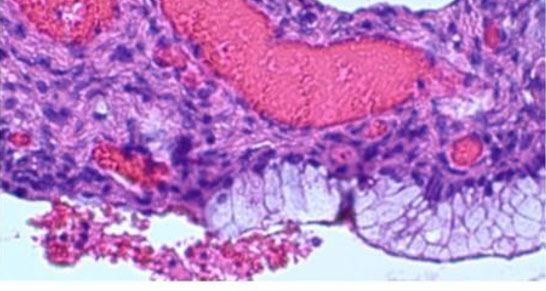

A 40-year-old pre-menopausal female presented with a history of menometrorrhagia characterized by increased uterine bleeding between menstrual cycles. Her medical history was significant for hypertension, type 2 diabetes mellitus, ulcerative colitis, rheumatoid arthritis, and PJS. Past medical procedures included two cesarean sections, urethral stents, and left ovarian cystectomy. Family history revealed paternal colorectal carcinoma, maternal endometrial cancer, and a sister with breast cancer. Histologic evaluation demonstrated abrupt transition between simple columnar ciliated epithelium into GI-epithelium (Figure 2), bland cytologic features without surgical complexity (Figure 3), and ubiquitous transitional areas between ciliated tubal epithelium and abnormal intestinal-like mucinous epithelium (Figure 4).

Histologic evaluation following the TAH-BSO demonstrated areas of abrupt transition between normal ciliated tubal epithelium and intestinal-like mucinous epithelium (Figure 2). Although the findings included metaplasia and benign cytologic changes (Figure 3), the mild architectural complexity observed (Figure 4) necessitated further clinical investigation to exclude neoplastic secondary changes. Negative cancer screening included colonoscopy, mammograms, endometrial biopsy, and pap smears. Appendiceal pathology was excluded through imaging studies.

Figure 3: H&E stain (400×) showing bland cytological features, consistent with absence of nuclear pleomorphism, loss of polarity, pseudostratification and no mitotic bodies.